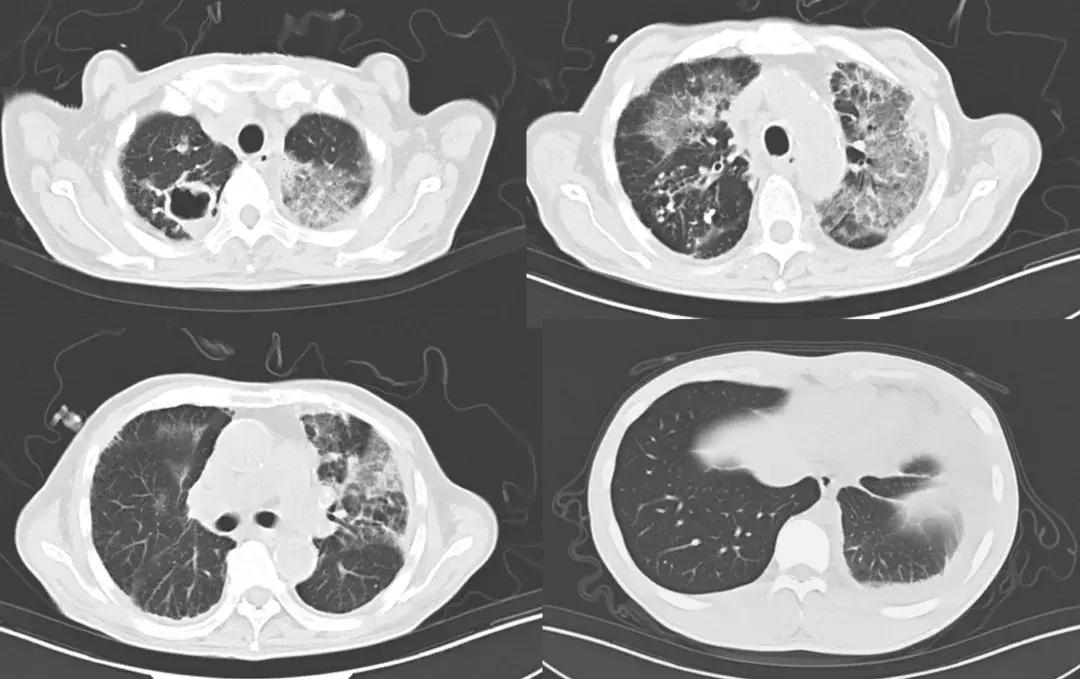

心电图:正常心电图;B超:胆囊显示不清,双侧胸腔积液(左侧见深约27mm无回声区,右侧见深约12mm无回声区,胰腺、脾脏、双肾未见明显异常。外院胸部CT(2018-7-19)示:右肺上叶及左肺下叶多发厚壁空洞,右肺上叶及两肺下叶炎症改变。(图1)

图1